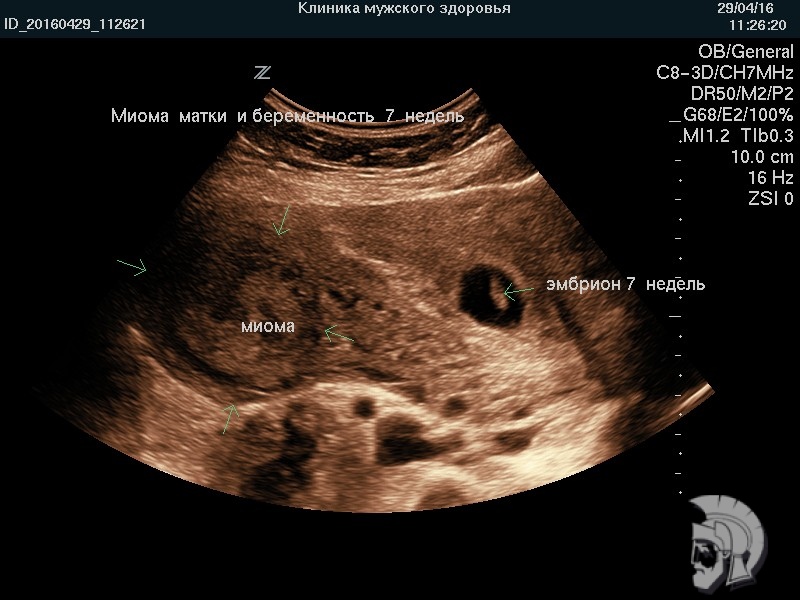

| Фото миомы матки и беременности 7 недель |